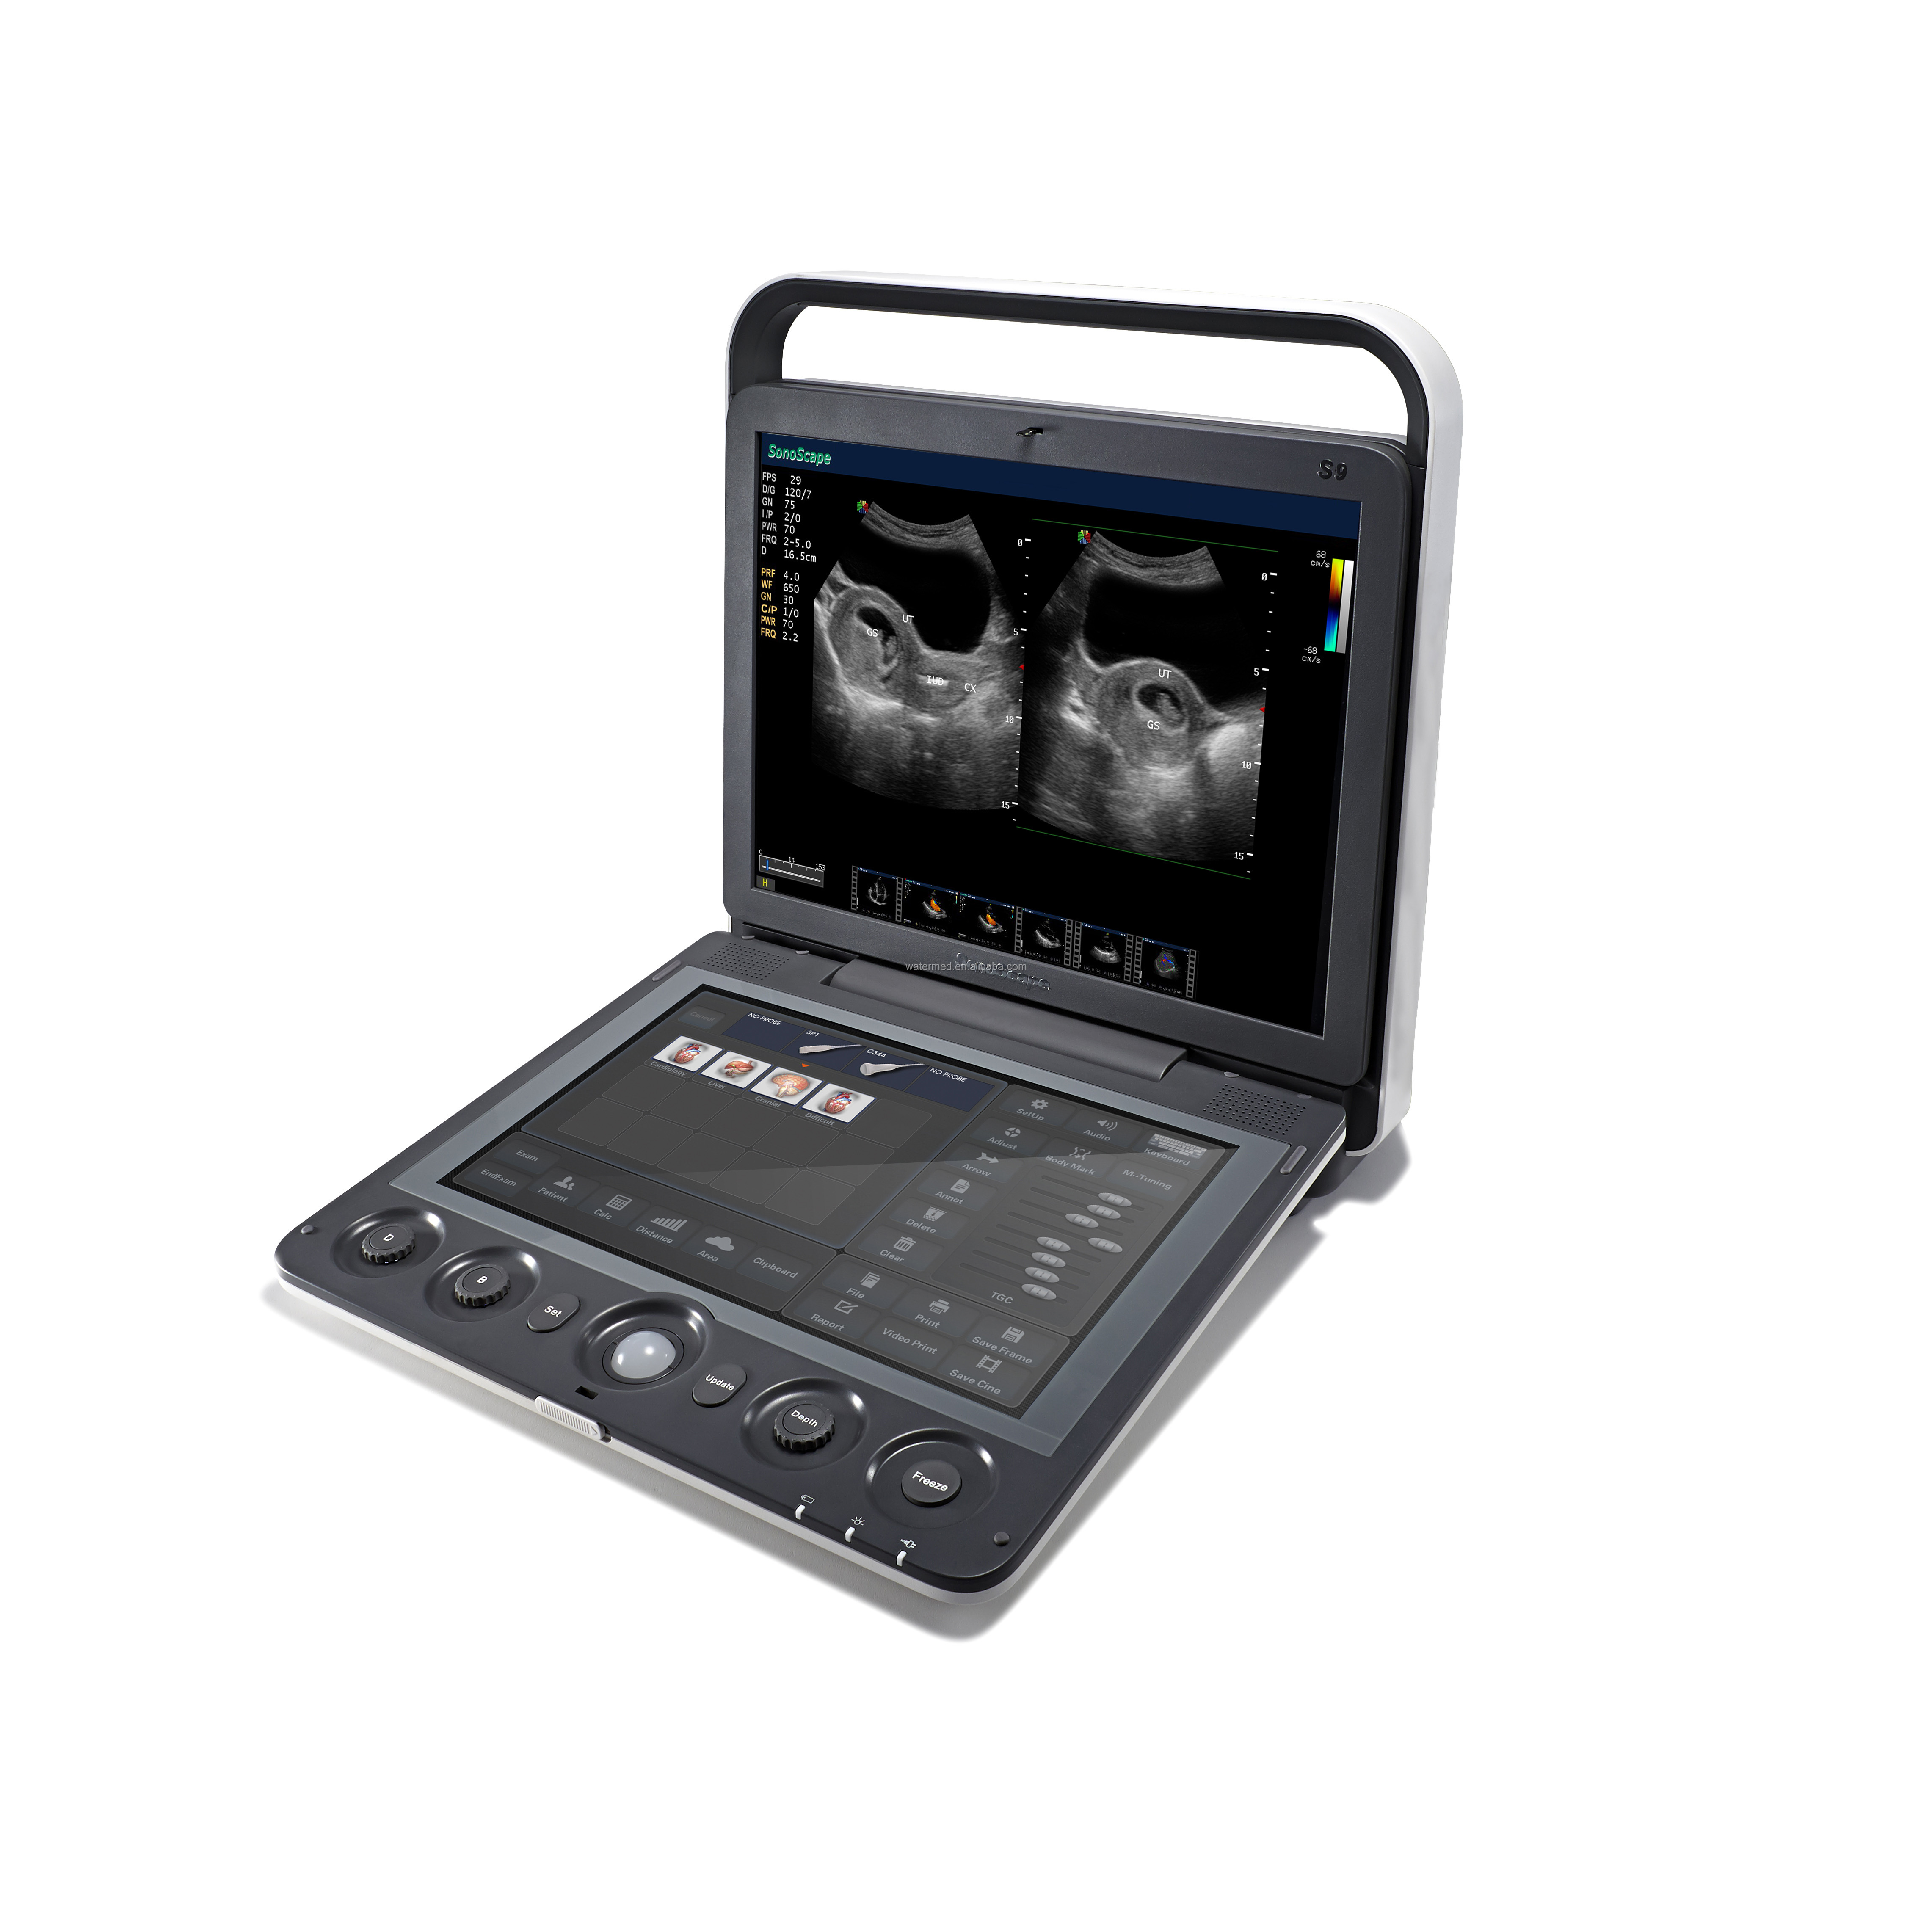

Portable 3D 4D Color Doppler USG&Sonoscape S9

SonoScape has been in the field of ultrasound since releasing the first portable color Doppler ultrasound system. From this dedication, a large number of ultrasound technologies have emerged, especially in hand-held systems. Out of this dedication, the S9 was released as a powerful and versatile imaging platform with a futuristic design. Small in size and wide in application, the S9 is suitable for Cardiology, Radiology, Abdominal, Obstetrics, Small Parts and Urology, providing the best solution for ultrasound imaging with outstanding performance.